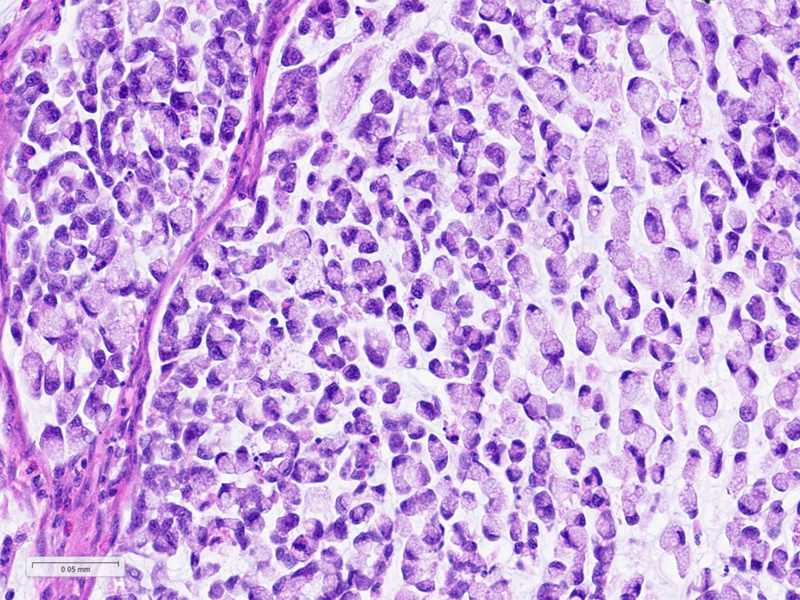

Histologically, the tumour was confirmed to be an adenocarcinoma invading through the gastric submucosa into the muscularis propria (Panel A), showing multiple architectural patterns. While the majority of the lesion displayed a tubular and papillary arrangement of neoplastic cells (Panel B), there were also mucin pools containing floating tumour cells (Panel C), as well as areas of discohesive signet-ring cells (Panel D), so called for their intracytoplasmic mucin droplet that eccentrically displaces the nucleus. The different architectural patterns were not entirely independent of each other nor were they intermingled, but rather arranged side by side (Panel E).

While gastric adenocarcinomas may exhibit intratumoral architectural heterogeneity, a lesion that displays a mixture of different histological subtypes and one of them is a signet-ring cell/poorly cohesive carcinoma is classified as a mixed carcinoma, mixed adenocarcinoma or mixed-type carcinoma/adenocarcinoma.